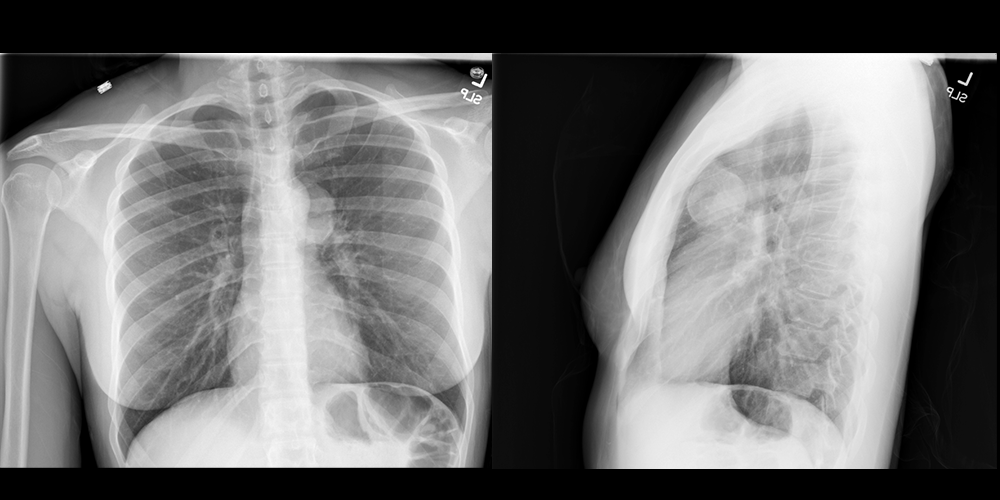

A chest X-ray may reveal sequelae of COPD like hyperinflated lungs with increased A-P diameter and those of heart failure like cardiomegaly, pulmonary edema, and pleural effusions

Pertinent Imaging Observations

Click on the links below to view images from the study, and assess these key findings as best you can.

Second Imaging Study

What is the next imaging study you will order?